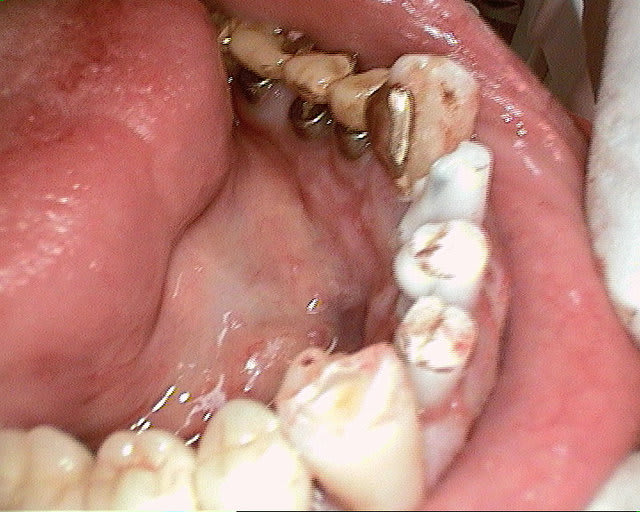

merci pour tes réponses, pour ma part (expérience avec plus de 600 implantation immédiate) je ne pense pas qu'il va y avoir une résorption, car pas de lambeau et tu n'as pas mis de trop grande pression sur l'os buccal.Un exemple ci dessous implantation ( 4 semaines après extraction) avec un 4.5 que (oui déjà mis dans un autre post).J'ai d'autres exemples similaires en extraction implantation immédiate mais avec des implants 3.5mm.Si l'espace entre l'implant et l'os buccal est plus grand que 1mm j'ajoute du collagène et de l'acide hyaluronique pour accélérer la régénération.

dernière radio à un an après cémentation de la couronne.

Ce qui est non négligeable est d'avoir une stabilité primaire d'un minimum de 35Ncm et pas plus de 70Ncm.

un cas récent os vestibulaire très fin.